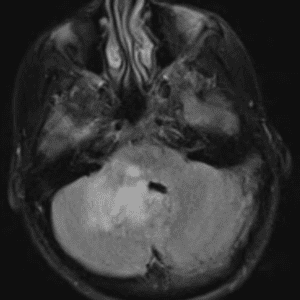

Case #58

Medulloblastoma